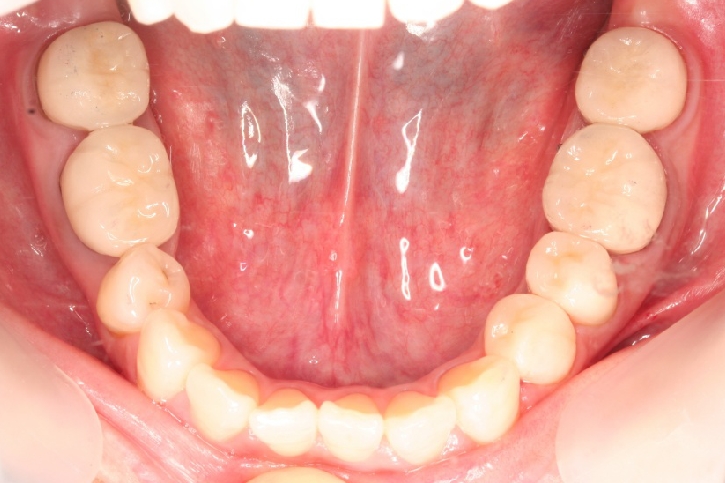

義歯修復

担当歯科医師:川津良介

2013年3月6日千葉県市原市 M.K様  金属床義歯修復